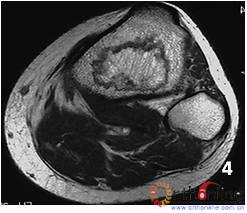

(三)    国内外的研究显示,在对股骨头坏死塌陷预测的方法中,以日本骨坏死研究会(Japanese investigation committeeJIC)依坏死部位对ONFH分型的准确性较高(图4)。本分型对JIC分型法进行改良,并对比。

4 日本骨坏死研究会依坏死部位分型

Fig 4 Japanese investigation committee (JIC) classification for ONFH